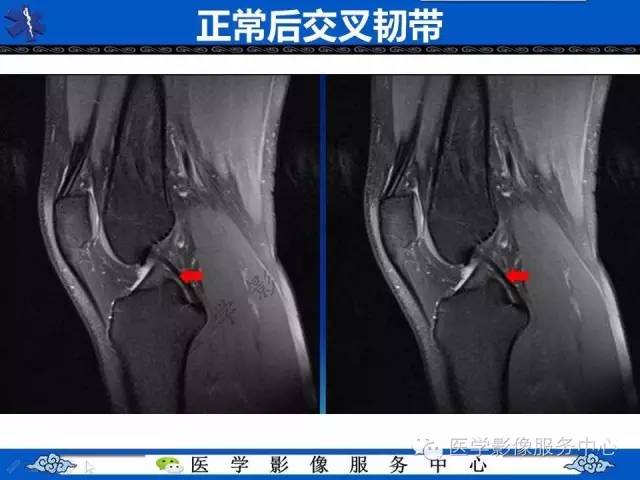

【影像征象】双后交叉韧带征